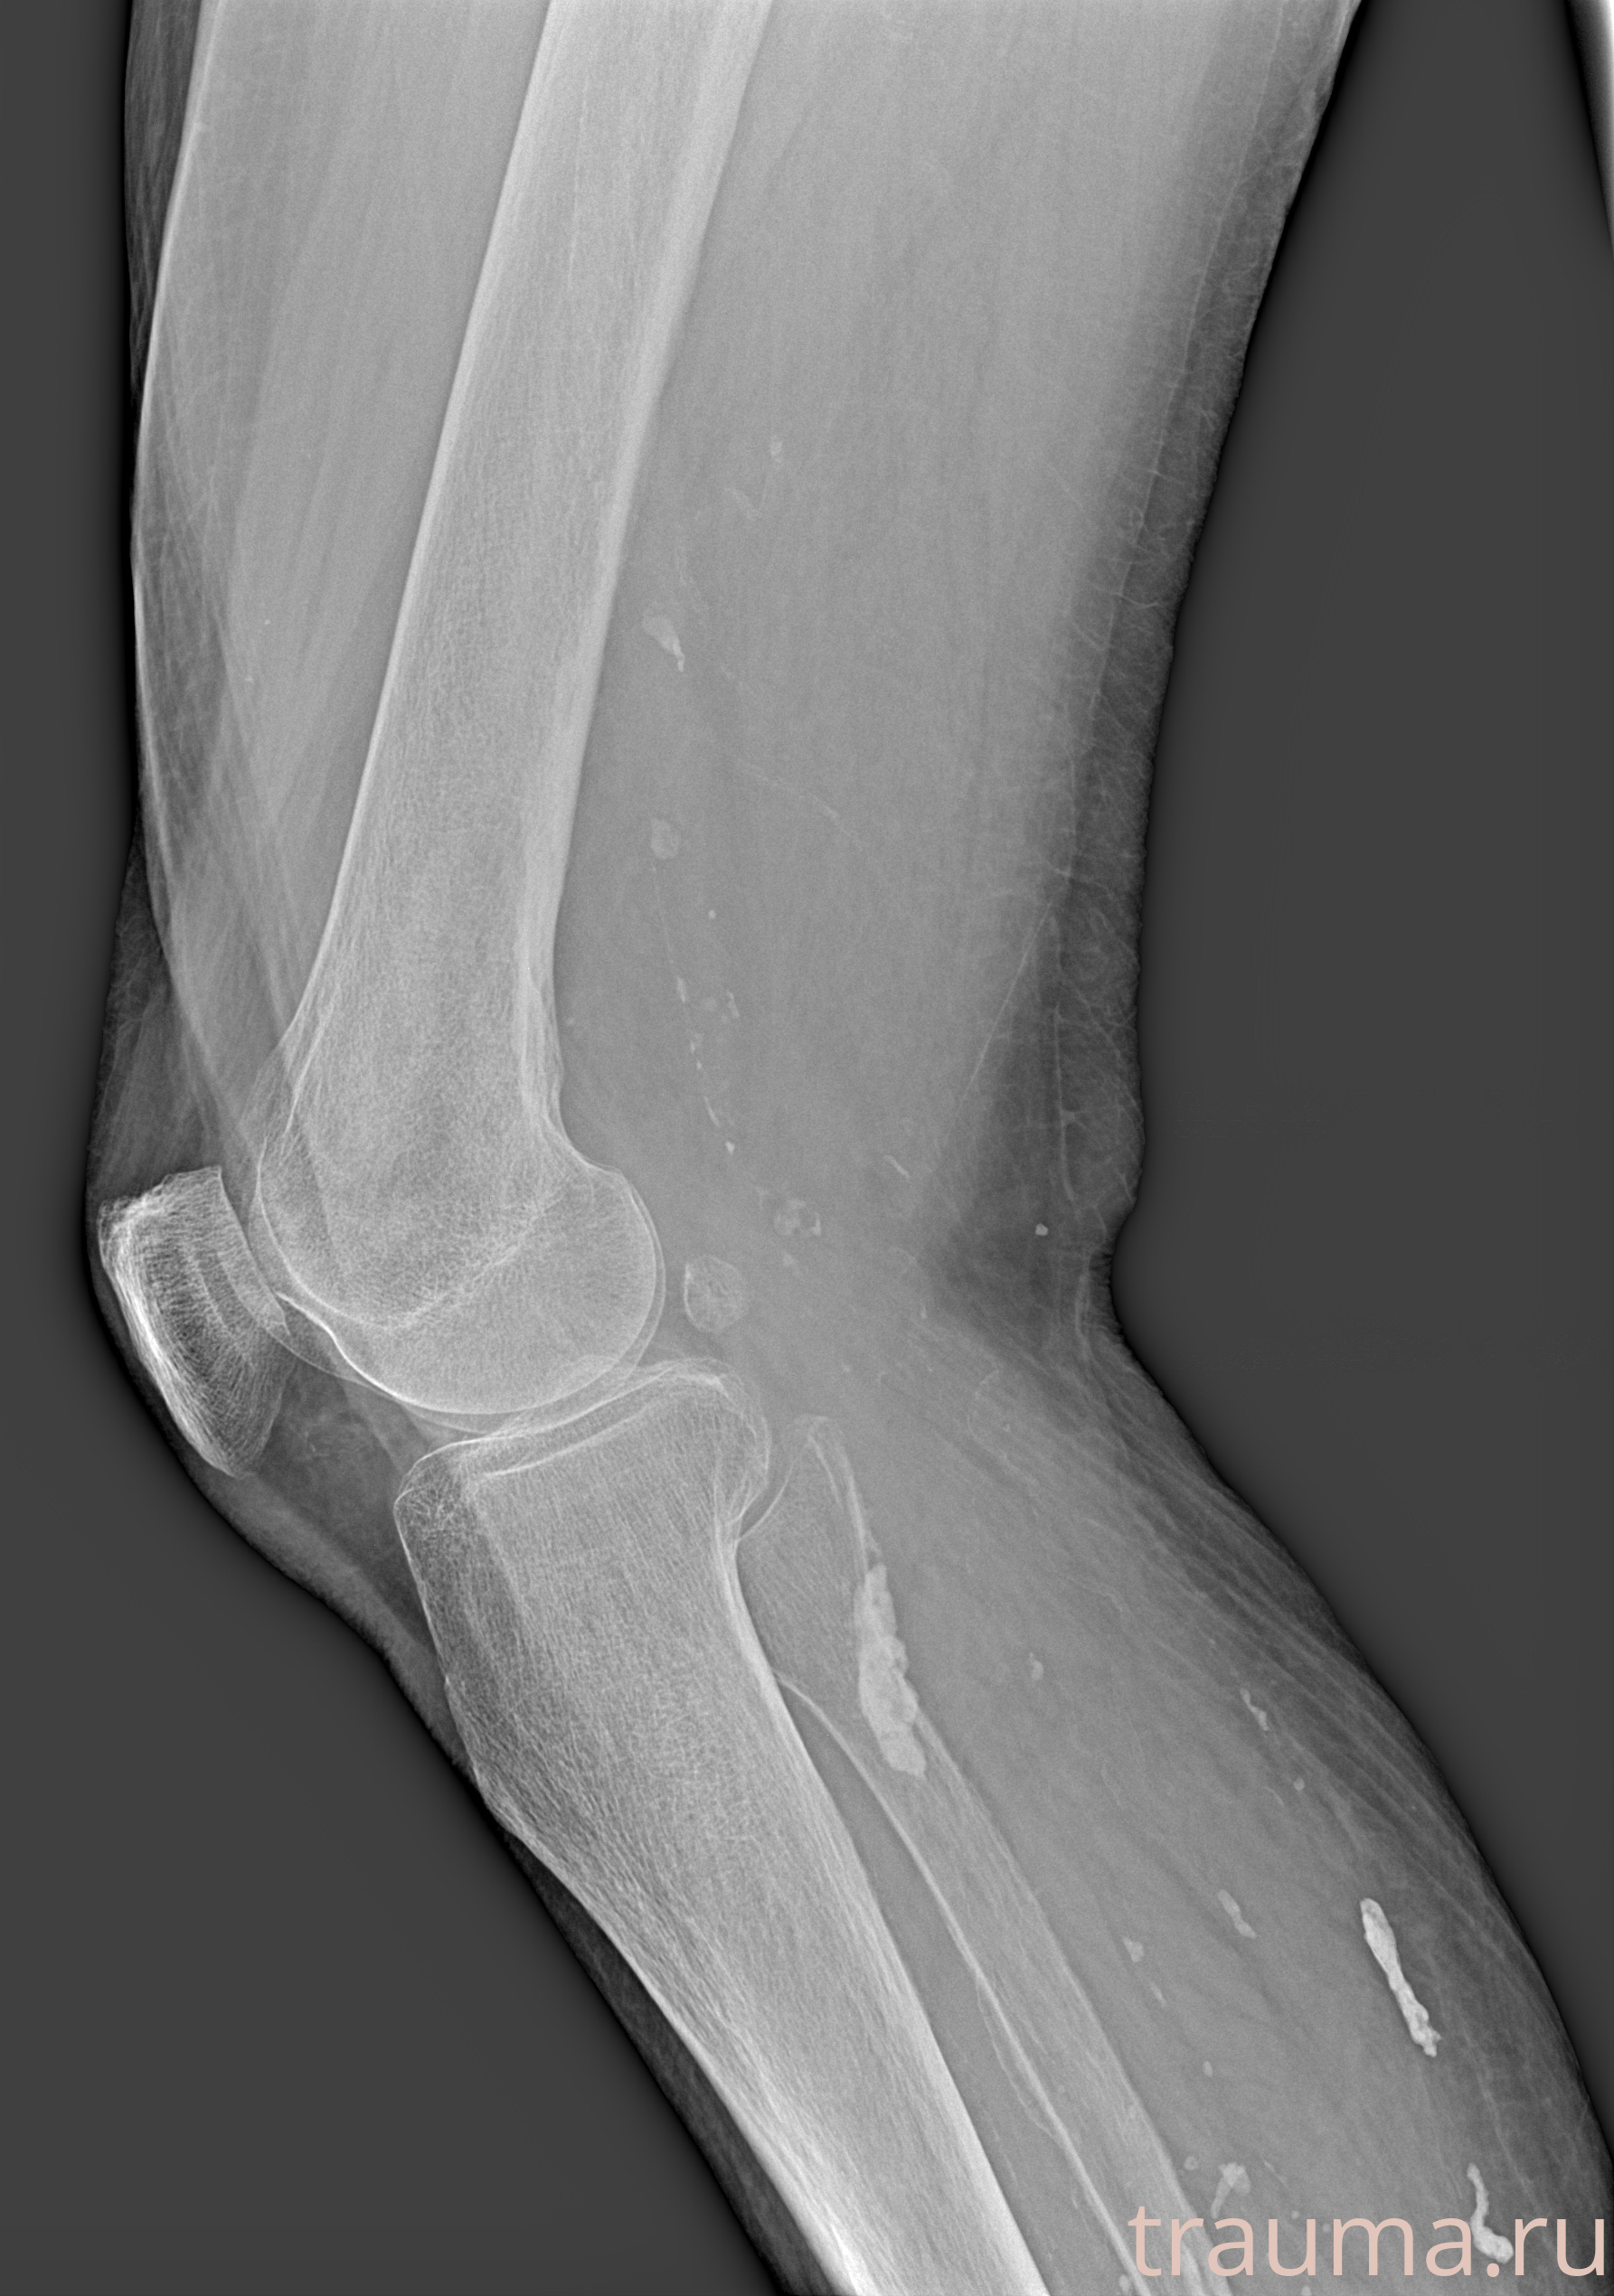

Рентгенограммы

Рентген на дому: по вашему адресу приезжает врач-рентгенолог, травматолог-ортопед с мобильным рентгеновским аппаратом, проводит диагностику травмы или заболевания, делает необходимые рентгенограммы, дает рекомендации по дальнейшему лечению. Получить качественные снимки в домашних условиях возможно благодаря уникальной методике, разработанной МосРентген Центром для института  Склифосовского